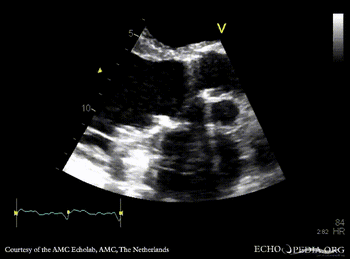

Abscess of aortic valve prosthesis

PLAX: Abscess of aortic valve prosthesis PLAX with Color Doppler